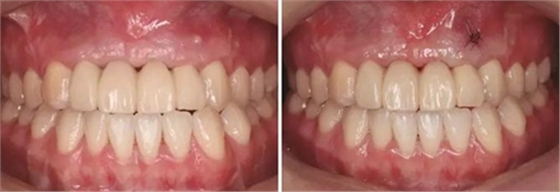

圖17 CBCT測(cè)量骨量變化 圖18 早期修復(fù)戴牙當(dāng)天

圖19 早期修復(fù)1月 圖20 早期修復(fù)2月

圖21 早期修復(fù)3月 圖22 早期修復(fù)3月打開三角間隙

圖23 早期修復(fù)4月 圖24 早期修復(fù)7月切除軟組織增生后

圖25 早期修復(fù)7月調(diào)改橋體部形態(tài)為卵圓形并高度拋光 圖26 早期修復(fù)8月

圖27 早期修復(fù)8月調(diào)改后 圖28 早期修復(fù)10月